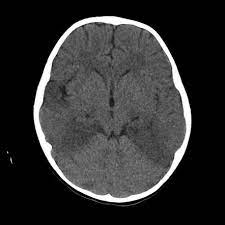

Two subtypes are recognized which differ in demographics, virus, and pattern of involvement. Become a gold supporter and see no ads. Bilateral temporal lobe t2 hyperintensity refers to hyperintense signal involving the temporal lobes on t2 weighted and flair imaging. Hypertrophic pachymeningitis is a condition where there is localized inflammatory thickening of the dura. Limbic encephalitis, mca ischaemia, tumours, effects of seizures) hyperintense t2 signal in the medial temporal lobes, inferior frontal lobes and insula basal ganglia are usually spared Reference osborn a, et al. Given the history of fever and seizures coupled with the mri findings of bilateral mesial temporal lobe changes, herpes encephalitis requires clinical consideration. The changes spare the basal ganglia, a feature which is helpful in distinguishing an mca infarct with hemorrhagic transformation from herpes simplex encephalitis, the diagnosis in this case. Mri demonstrates extensive edema in the right temporal lobe with areas of intrinsic high t1 signal, in keeping with hemorrhage. It is estimated to occur in ~2% of pati. The differential diagnoses include limbic encephalitis (paraneoplastic), gliomatosis cerebri, and status epilepticus. It is reasonable to obtain an mri when patients are asymptomatic to ensure that no other abnormality is present which may be causing a recurrent chemical meningitis (e.g. Axial t2 prominent swelling, increase t2 signal involving the left temporal lobe and insular cortex.

Herpes simplex encephalitis typically manifests in older adults (about 50% of cases) with headache, fever, altered sensorium, and even seizure.

Mri demonstrates extensive edema in the right temporal lobe with areas of intrinsic high t1 signal, in keeping with hemorrhage. Become a gold supporter and see no ads. For a general discussion, and for links to other system specific manifestations, please refer to the article on coccidioidomycosis. This patient went on to have hsv encephalitis proven on csf pcr. This patient went on to have hsv encephalitis proven on csf pcr. Spinal hydatid disease is an uncommon manifestation of hydatid disease, caused by the larval stage of echinococcus granulosus, or less commonly e. Given the history of fever and seizures coupled with the mri findings of bilateral mesial temporal lobe changes, herpes encephalitis requires clinical consideration. Multilocularis, and describes a spectrum of disease involving the spinal cord, the spine, or both. Herpes simplex encephalitis radiology case radiopaedia mri demonstrates extensive edema in the right temporal lobe with areas of intrinsic high t1 signal, in keeping with hemorrhage. Hsv encephalitis | radiology case | radiopaedia.org. Two subtypes are recognised which differ in demographics, virus, and pattern of involvement. It is estimated to occur in ~2% of pati. Reference osborn a, et al.